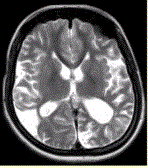

问题 女性,22岁。癫痫发作及智力异常。MRI显示见下图。 关于该病描述正确的是

选项 A.脑萎缩 B.双侧顶枕叶软化灶 C.蛛网膜囊肿 D.双侧顶枕叶脑梗死 E.脑积水 F.脑炎

答案 AB